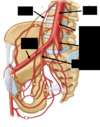

Where is the broad ligament

What is the broad ligament made up of?

Double layer of peritoneum

What is the function of the broad ligament?

Maintains uterus in the midline

What is contained within the broad ligament?

Uterine tubes

Proximal round ligament

What does the round ligament attatch to?

Lateral aspect of uterus

through deep inguinal ring

superficial tissue of the female perineum

Where is the round ligament?

What supports the utereus in place?

Uterosacral ligaemnts

Endopelvic fascia

Levator ani